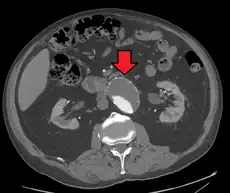

A ruptured AAA with an open arrow marking the aneurysm and the closed arrow marking the free blood in the abdomen